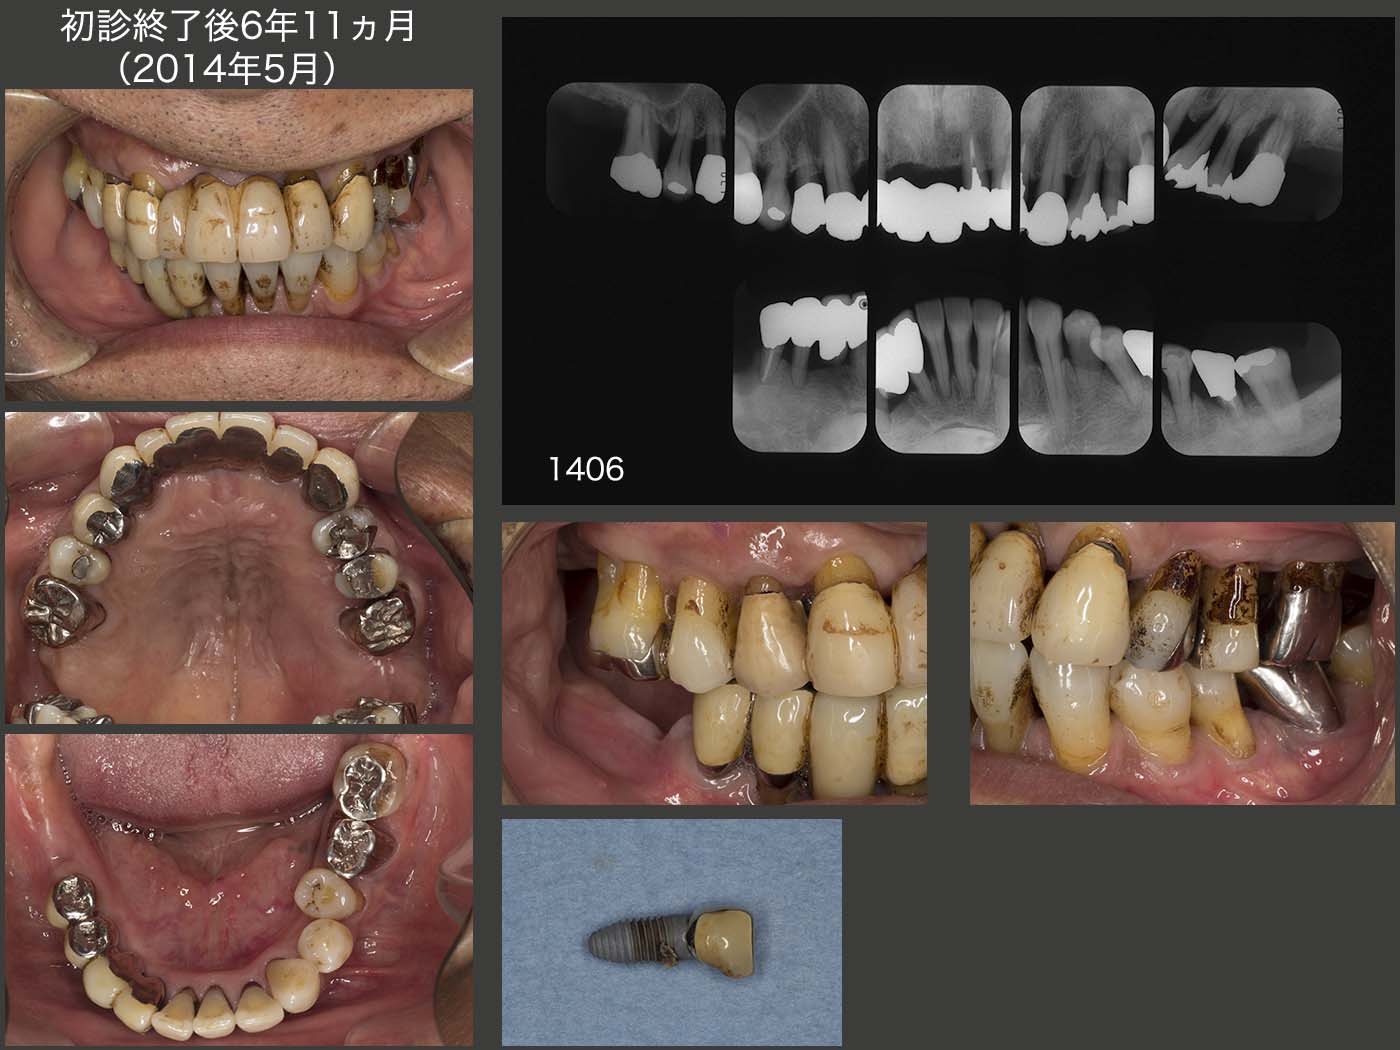

2014年5月,6年ぶりに,インプラントが脱落したとのことで来院された.私としては,よくここまで保ったものだと逆に感心してしまった.(私の稚拙な手技で早期に脱落してしまったことに対しては,本当に申し訳ない.)右上7は自然脱落したとのこと.

右下のブリッジの動揺は著しく,右側での咀嚼は難しく,左側のみの咀嚼にならざるを得ない状況であった.その結果,上顎左側の歯周病が進行してしまった.特に,左上4の近心は9mm,左上6は全周に10mmの歯周ポケットがみられた.